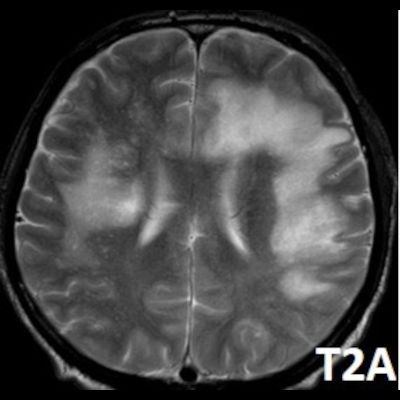

- Bilateral asimetrik subkortikal ve derin beyaz cevherde T1 ağırlıklı görüntülerde belirgin hipointens (oklar), T2A görüntülerde hiperintens (oklar), gri cevhere bakan kesimi düzgün (oklar), DAG’de hiperintens (ok) lezyonlar izlendi. Lezyonlarda T2/FLAIR uyumsuzluğu vardı (ok). Serebellar beyaz cevherde dentat nukleusu koruyan hilal işareti görüldü (ok başı). SWI sekansta sol motor kortekste hipointens kronik glioinflamatuar reaksiyon ile uyumlu sinyal değişikliği izlendi (ok başı).

- Çoğunlukla subkortikal beyaz cevherde ve U fiberlerde, asimetrik, genelde kitle etkisi yapmayan ve kontrastlanmayan demiyelinizan lezyonlar görülür. Korteks ve derin gri cevher tutulumu daha nadirdir.

- PML lezyonları, T1A görüntülerde belirgin hipointenstir. Gri cevhere bakan yüzleri keskin olup T2/FLAIR uyumsuzluğu önemli özelliğidir.